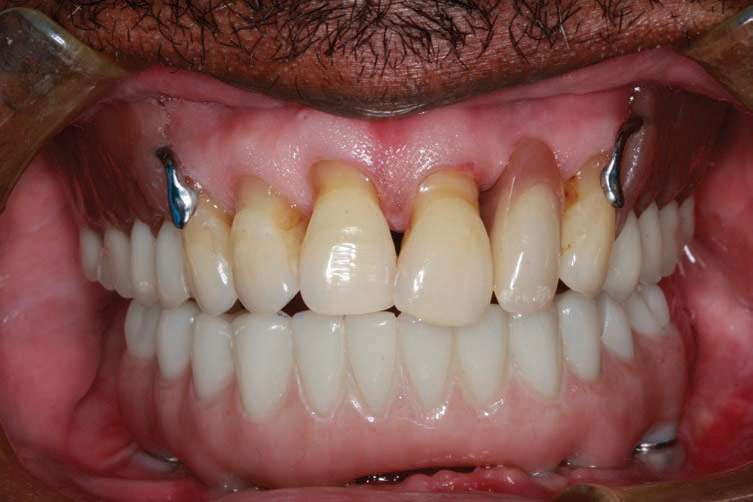

A patient presented with an ill-fitting upper partial denture opposing an ill-fitting lower complete denture. This patient had an epulis in the maxillary arch. Multiple frena were present, with high attachments in the lower arch that required pre-prosthetic modification prior to creating prototype prostheses that would be used to dictate implant placement (Figure 1). He reported no significant medical problems.

After the patient had the upper partial denture and lower denture fabricated and the vertical dimension of occlusion, aesthetics, and phonetics were verified, the approved lower denture was used as a vehicle for fiduciary markers so that a CBCT scan could be done. If needed, a surgical guide could be fabricated from a dual-scan protocol (Suremark) (Figure 4).